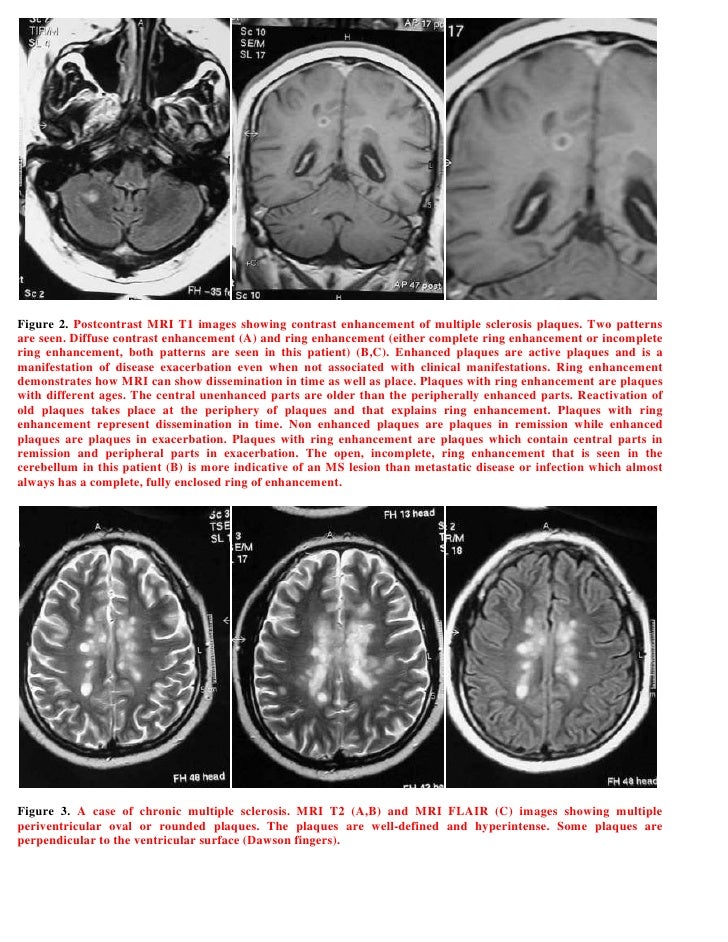

Magnetic resonance imaging (mri) of the brain is needed to detect the presence of white matter lesions.